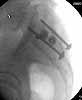

Patient was prone for procedure, as I thought too difficult to fix the wing in lateral position. Of course the repair of wing was easy, but reduction of SI very demanding. The Floro images document the residual lack of reduction. That was the closest I could get it using 6mm joystick in wing, and clamp on sacrum and clamp through notch.  The fixation was (initially) rigid. Anterior ex fix with supra-acetabular pins was placed due to condition of soft tissues, massive "beer-belly" overhanging the crest.

5. Your caudal iliosacral screw is/was in his spinal canal...it's low and posterior and the lateral fluoro image confirms this...a postop CT will show it (or it's trail at this point)...canal screws do not hold.